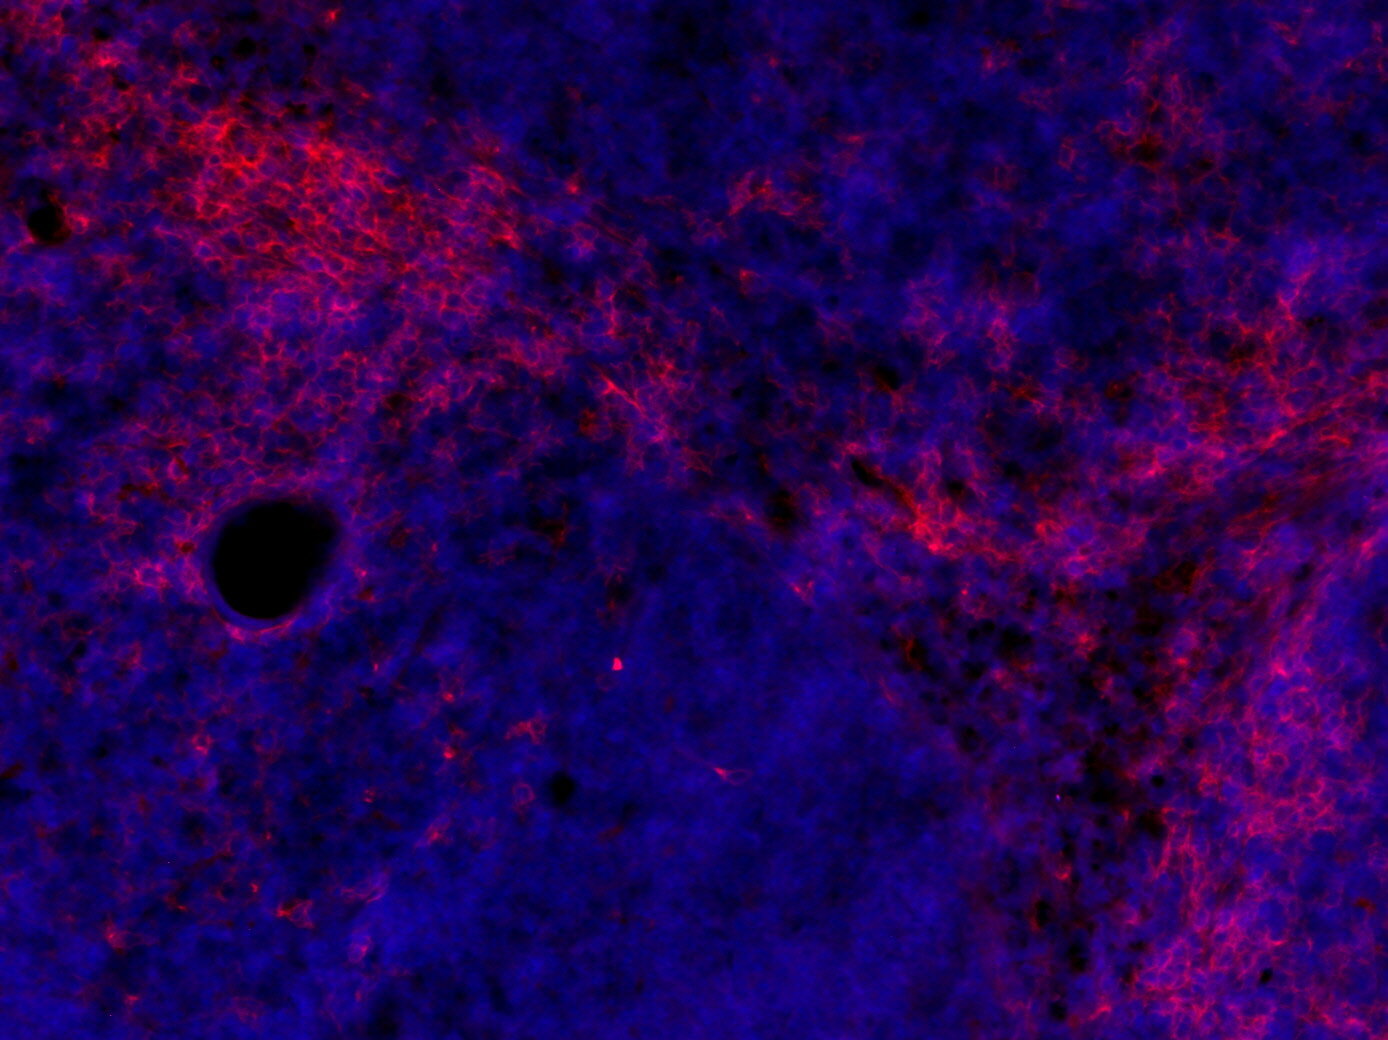

IHC-P: 1 : 50 up to 1 : 100 gallery

Immunohistochemistry (IHC-P) of formalin fixed, paraffin embedded (FFPE) tissue (some antibodies require special antigen retrieval steps, please refer to the ”Remarks” section). Immunoreactivity is usually revealed by fluorescence or a chromogenic substrate.

IHC: Antigen retrieval with citrate buffer pH 6 is required.